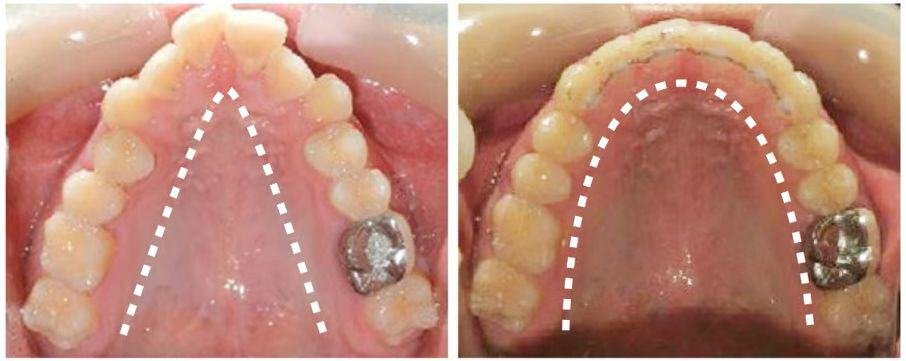

Misaligned teeth create hard-to-reach areas where plaque accumulates. Inadequate plaque removal leads to cavities and gum disease, which can be costly to treat and result in pain and tooth loss.

Misaligned teeth can cause uneven enamel wear and chipping. Correcting the bite can also alleviate bruxism (teeth grinding).